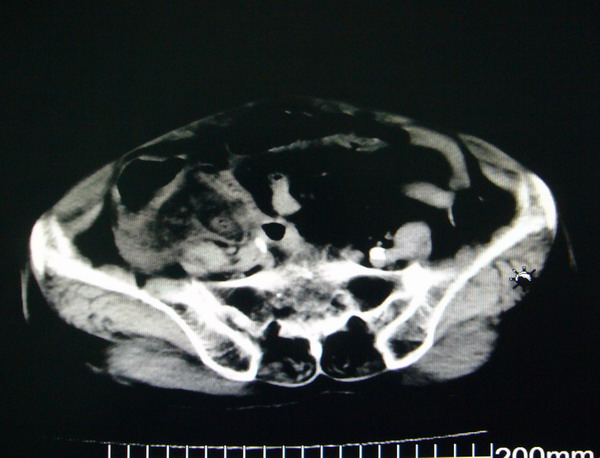

女:83y,转移性右下腹痛2小时,白细胞计数增高。

1.右侧肾盂扩大,肾盏无扩张,考虑:先天性肾盂变异可能性大。

2.胆囊扩张,考虑:胆囊炎。

3.阑尾区域可见以结节样高密度影,结合病史,考虑:阑尾结石,阑尾炎。

右下腹肠系膜增厚,结合病史支持阑尾炎.

右侧壶腹型肾盂可能,建议输路造影或增强

1.右侧肾盂扩大,考虑先天性肾盂变异或肾盂旁囊肿。

2.胆囊扩张,考虑胆囊炎。

3.阑尾区域可见结节样高密度影,结合病史考虑:阑尾结石、阑尾炎。